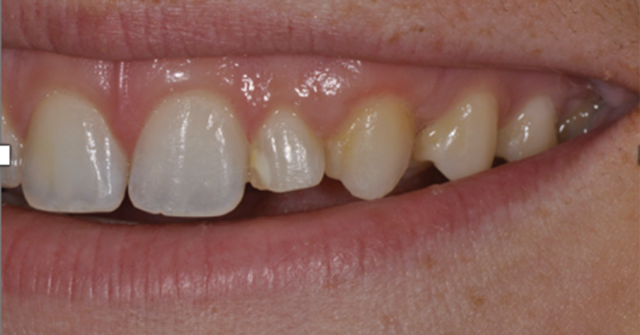

The guide’s most critical component is indicating the accurate gingival contour of the proposed final restoration. The surgeon uses this contour to visualize and measure implant-placement depth. The contouring is accomplished by fabricating a diagnostic wax-up.

The completed diagnostic wax-up must precisely outline the final gingival margin position, the position of the incisal edge and facial contour, and the embrasure form of the proposed restoration. The accuracy of these dimensions is essential for providing predictability to the outcome.